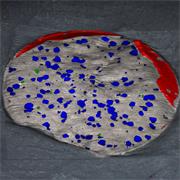

- Generate images of the formulations used in tablets, inhalers and nasal sprays at sub-micrometre spatial resolution

- Fast, quantitative analyses of entire tablets and powder blends

- Determine the uniformity of mixing

Generate images of formulations

Ensure your chemical images are representative; use Renishaw's StreamLine. You can change resolution to suit your domain size and, because Renishaw's WiRE software can cope with massive data files, you can analyse over the entire sample surface. Powerful Renishaw features, such as Slalom (to ensure the whole surface is sampled) and HD imaging (to get crisp clear images), provide all the options you need, whatever your formulation.